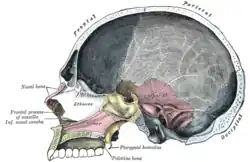

Corte sagital do crânio.

Corte sagital do crânio. -